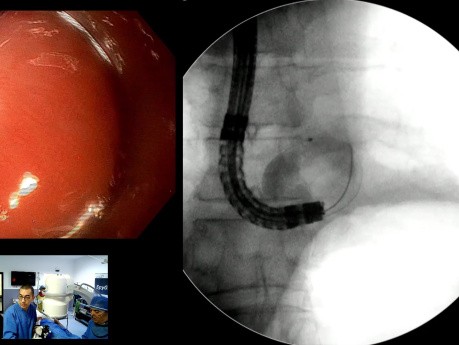

CPRE pour Calculs du Cholédoque de Grande Taille...

Cas vidéo endoscopique : homme de 55 ans atteint d'angiocholite aiguë.- sous traitement antidiabétique oral depuis 20 ans.- cholangite aiguë liée à un calcul de CBD de 14 x 25 mm. Cholécystectomie réalisée...